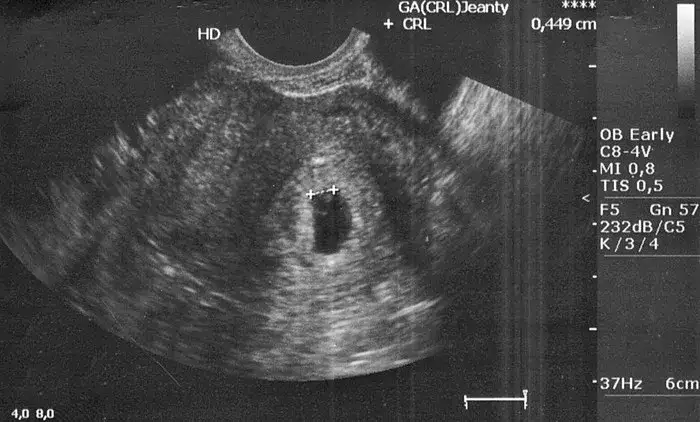

Po pozytywnym teście ciążowym naturalnie chcesz jak najszybciej umówić się na wizytę u ginekologa. Jednak w 4. tygodniu ciąży na USG prawdopodobnie zobaczysz jedynie pęcherzyk ciążowy, a zarodek i akcja serca mogą być jeszcze niewidoczne. To może wywołać niepotrzebny stres i niepokój. Zazwyczaj zaleca się, aby pierwsza wizyta u ginekologa odbyła się między 6. a 8. tygodniem ciąży. W tym czasie jest już duża szansa, że lekarz będzie mógł potwierdzić ciążę, zobaczyć zarodek i, co najważniejsze, usłyszeć bicie serca maleństwa. Dzięki temu unikniesz frustracji i niepewności związanej z zbyt wczesnym badaniem.